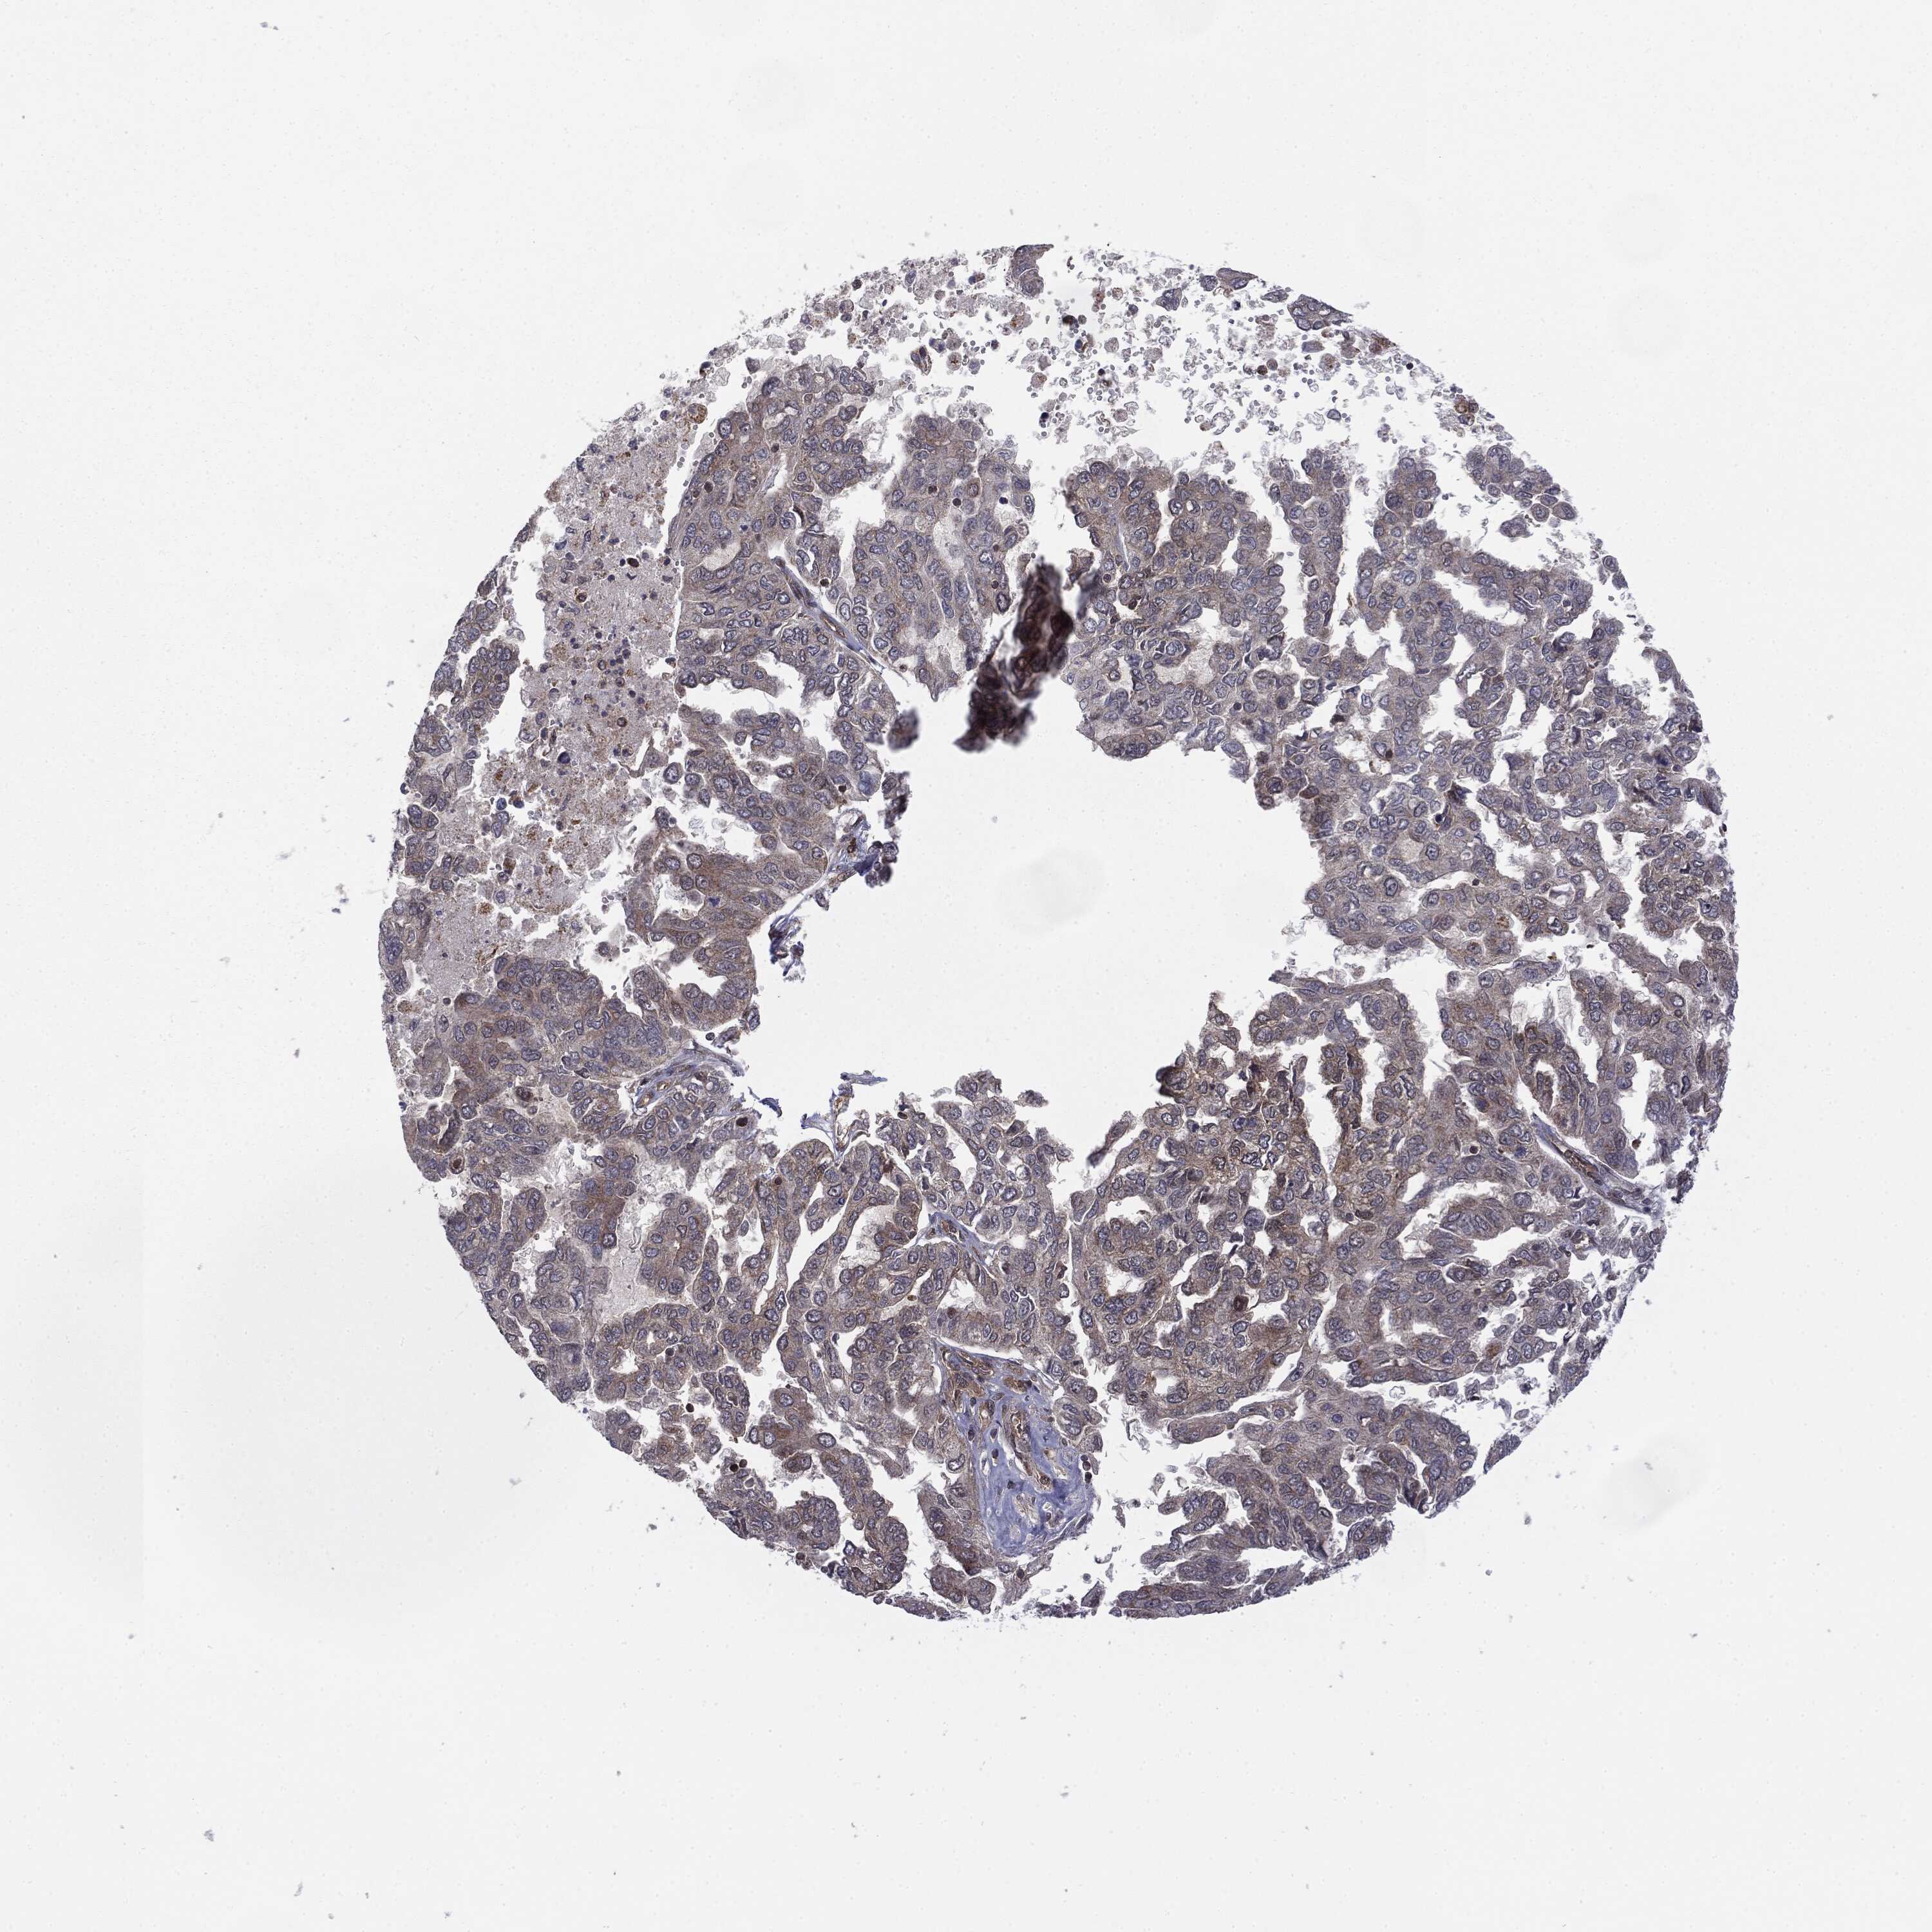

OVARIAN CANCER - Protein expressioni

A mouse-over function shows sample information and annotation data. Click on an image to view it in a full screen mode. Samples can be filtered based on level of antibody staining by selecting one or several of the following categories: high, medium, low and not detected. The assay and annotation is described here.

Note that samples used for immunohistochemistry by the Human Protein Atlas do not correspond to samples in the TCGA dataset.

Antibody stainingi

Antibody staining in the annotated cell types in the current human tissue is reported as not detected, low, medium, or high, based on conventional immunohistochemistry profiling in selected tissues. This score is based on the combination of the staining intensity and fraction of stained cells.

Each image is clickable and will lead to virtual microscopy that enables deeper exploration of all samples and also displays staining intensity scores, fraction scores and subcellular localization as well as patient and tissue information for each sample.

Cystadenocarcinoma, serous, NOS

Cystadenocarcinoma, mucinous, NOS

Carcinoma, endometroid